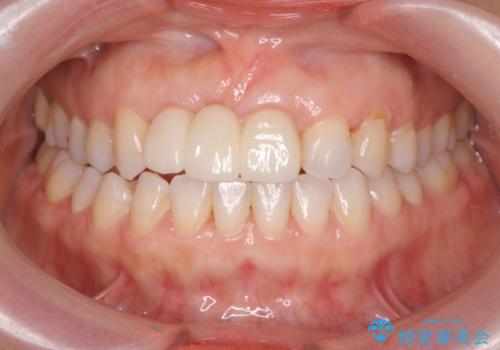

外れやすい前歯のブリッジ しっかりとした治療を受けたい

- 前歯のブリッジがすぐに外れる、歯ぐきが腫れている、見た目を良くしたい、と希望され来院されました。

歯周外科をおこなったことで歯ぐきのラインを整え、脱離しないような前歯のブリッジを作製することができました。